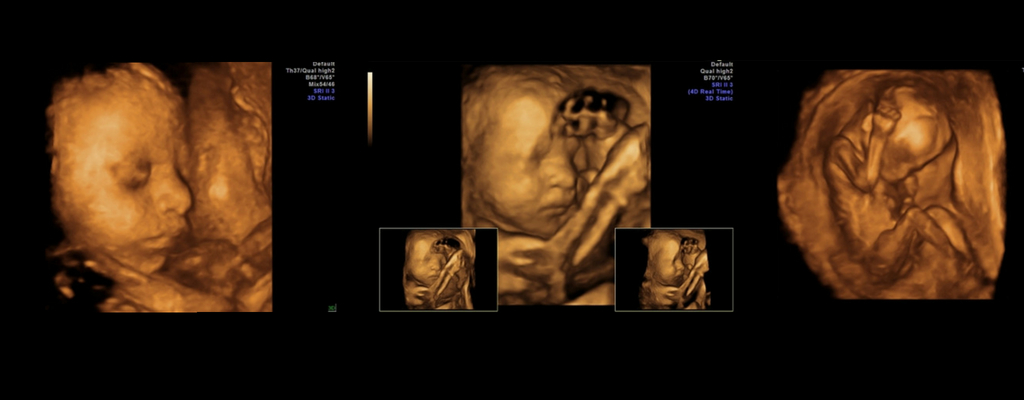

- 80% din examinarea ecografică propriu-zisă se realizează în modul 2D, însă ecograful cu capabilități 3D/4D sporește calitatea imaginii 2D analizate de medic cu până la 40%;

- Modulul de examinare în 3D/4D este folosit la finalul detalierii morfologice. Softul 3D/4D ne oferă imagini tridimensionale cu fătul în timp real, ce pot fi oferite pacientei pe CD. Imagini clare și de calitate pot fi obținute și dacă fătul îi oferă examinatorului ferestre ecografice optime pentru imagini de înaltă calitate 3D/4D;

Ce înseamnă morfologie fetală 3d/4d

Dr. Cristian Nicolae, medic primar Radiologie și Imagistică Medicală explică rolul Ecografiei de Sarcină 3D/4D, ca element complementar Ecografiei de Sarcină 2D. Mămicile trebuie să știe că softul 3D/4D crește cu până la 40% performanța modulului 2D, dar modulul 2D rămâne singura modalitate de analiză a dezvoltării anatomice a fătului.

ROL EMOȚIONAL: „Ecografia 3D/4D reprezintă un beneficiu atunci când se dorește identificarea anumitor detalii și atunci când părinții sunt nerăbdători să-și vadă copilul din burtică și să-i analizeze trăsăturile! Aceasta creează un efect video live, similar unui film, cu bebelușul din burtica mamei și este o modalitate de apropiere a părinților de viitorul lor copil. Mai ales că, imaginea obținută prin examinarea 3D/4D de la 32-34 de săptămâni de sarcină este identică cu cea bebelușului pe care mama îl ia în brațe după naștere.”

ROL EDUCATIV: „Această examinare permite evidențierea și înțelegerea de către părinți a eventualelor malformații ale fătului – membre, coloană vertebrală, față, craniu. Ele pot fi mult mai ușor arătate și explicate părinților. Ecografia 3D/4D nu constituie o metodă de diagnostic a problemelor de sănătate ale copilului, însă poate contribui cu informații suplimentare privind o anormalitate deja constatată în timpul ecografiei 2D.”